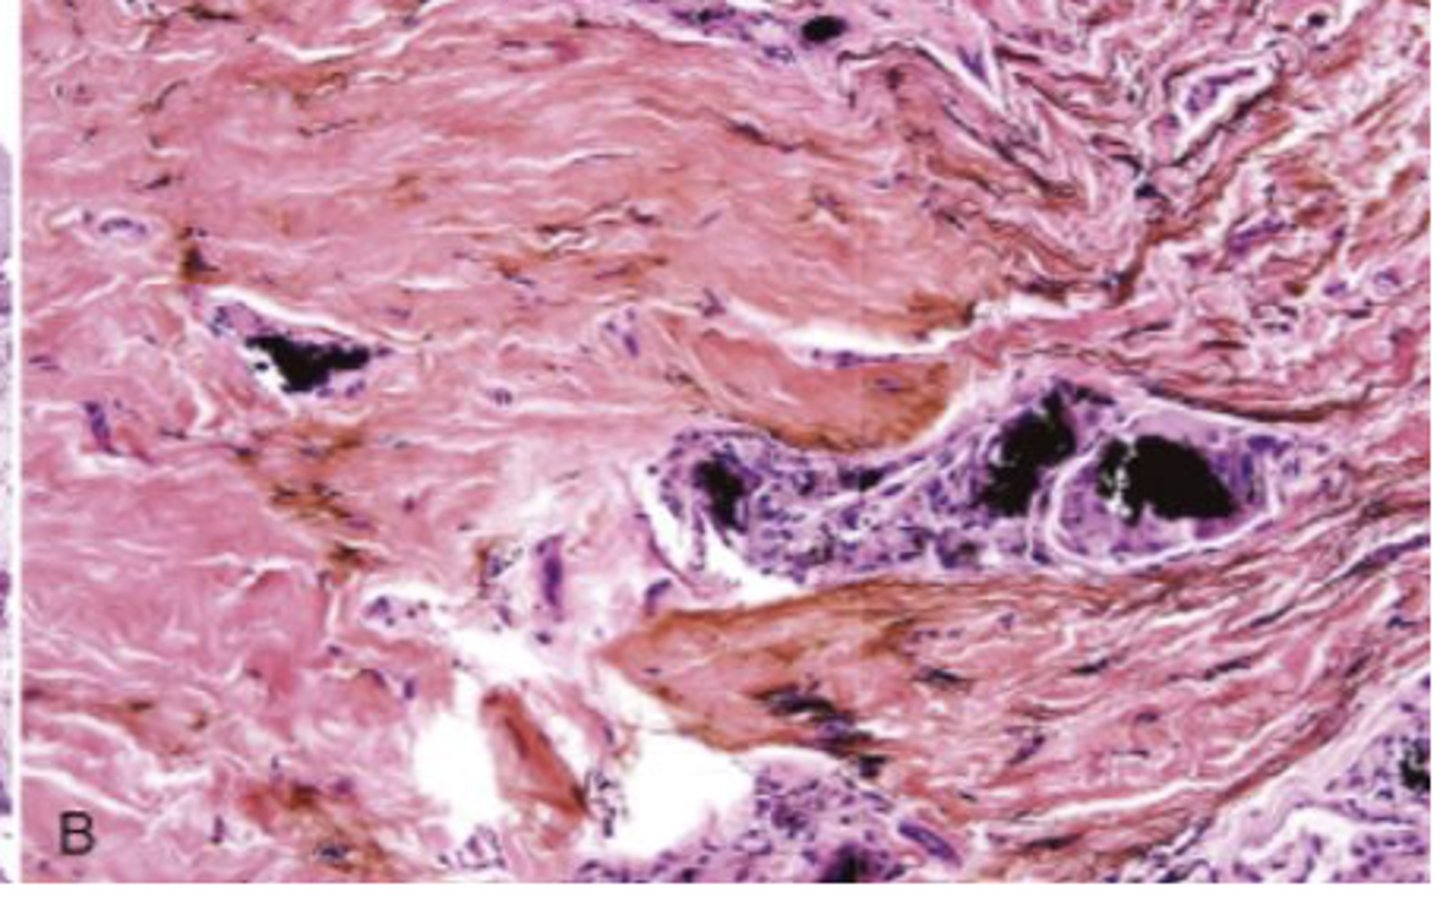

What are the black particles embedded in the purple?

amalgam in scar tissue

These are histopathologic features of what?

- Pigmented fragments

- Staining of reticulin fibers

- Large fragments surrounded by fibrosis

amalgam tattoos